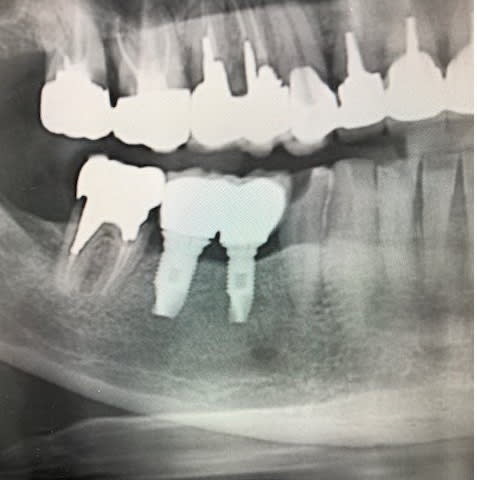

il me semble que ce sont des implants 3i

Qu'en pensez-vous?

çà semble cohérent avec du 3i

maintenant si tu veux qu'on soit sûr à 100%, tu nous fais une belle rétro....on verra bien mieux les fins détails de "l'anatomie" de ces implants que sur un crop de pano....

Effectivement l'image est une capture de panoramique que m'a envoyé un ami.

Je vais voir s'il peut faire une belle rétro-alvéolaire.